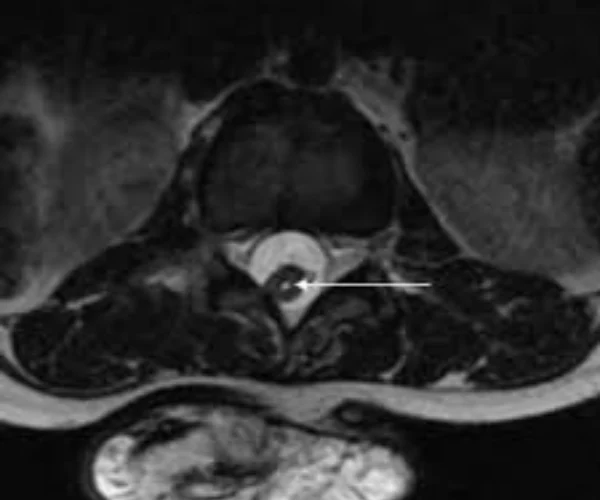

- Split cord malformation

- Tethered cord syndrome

Split Cord Syndrome